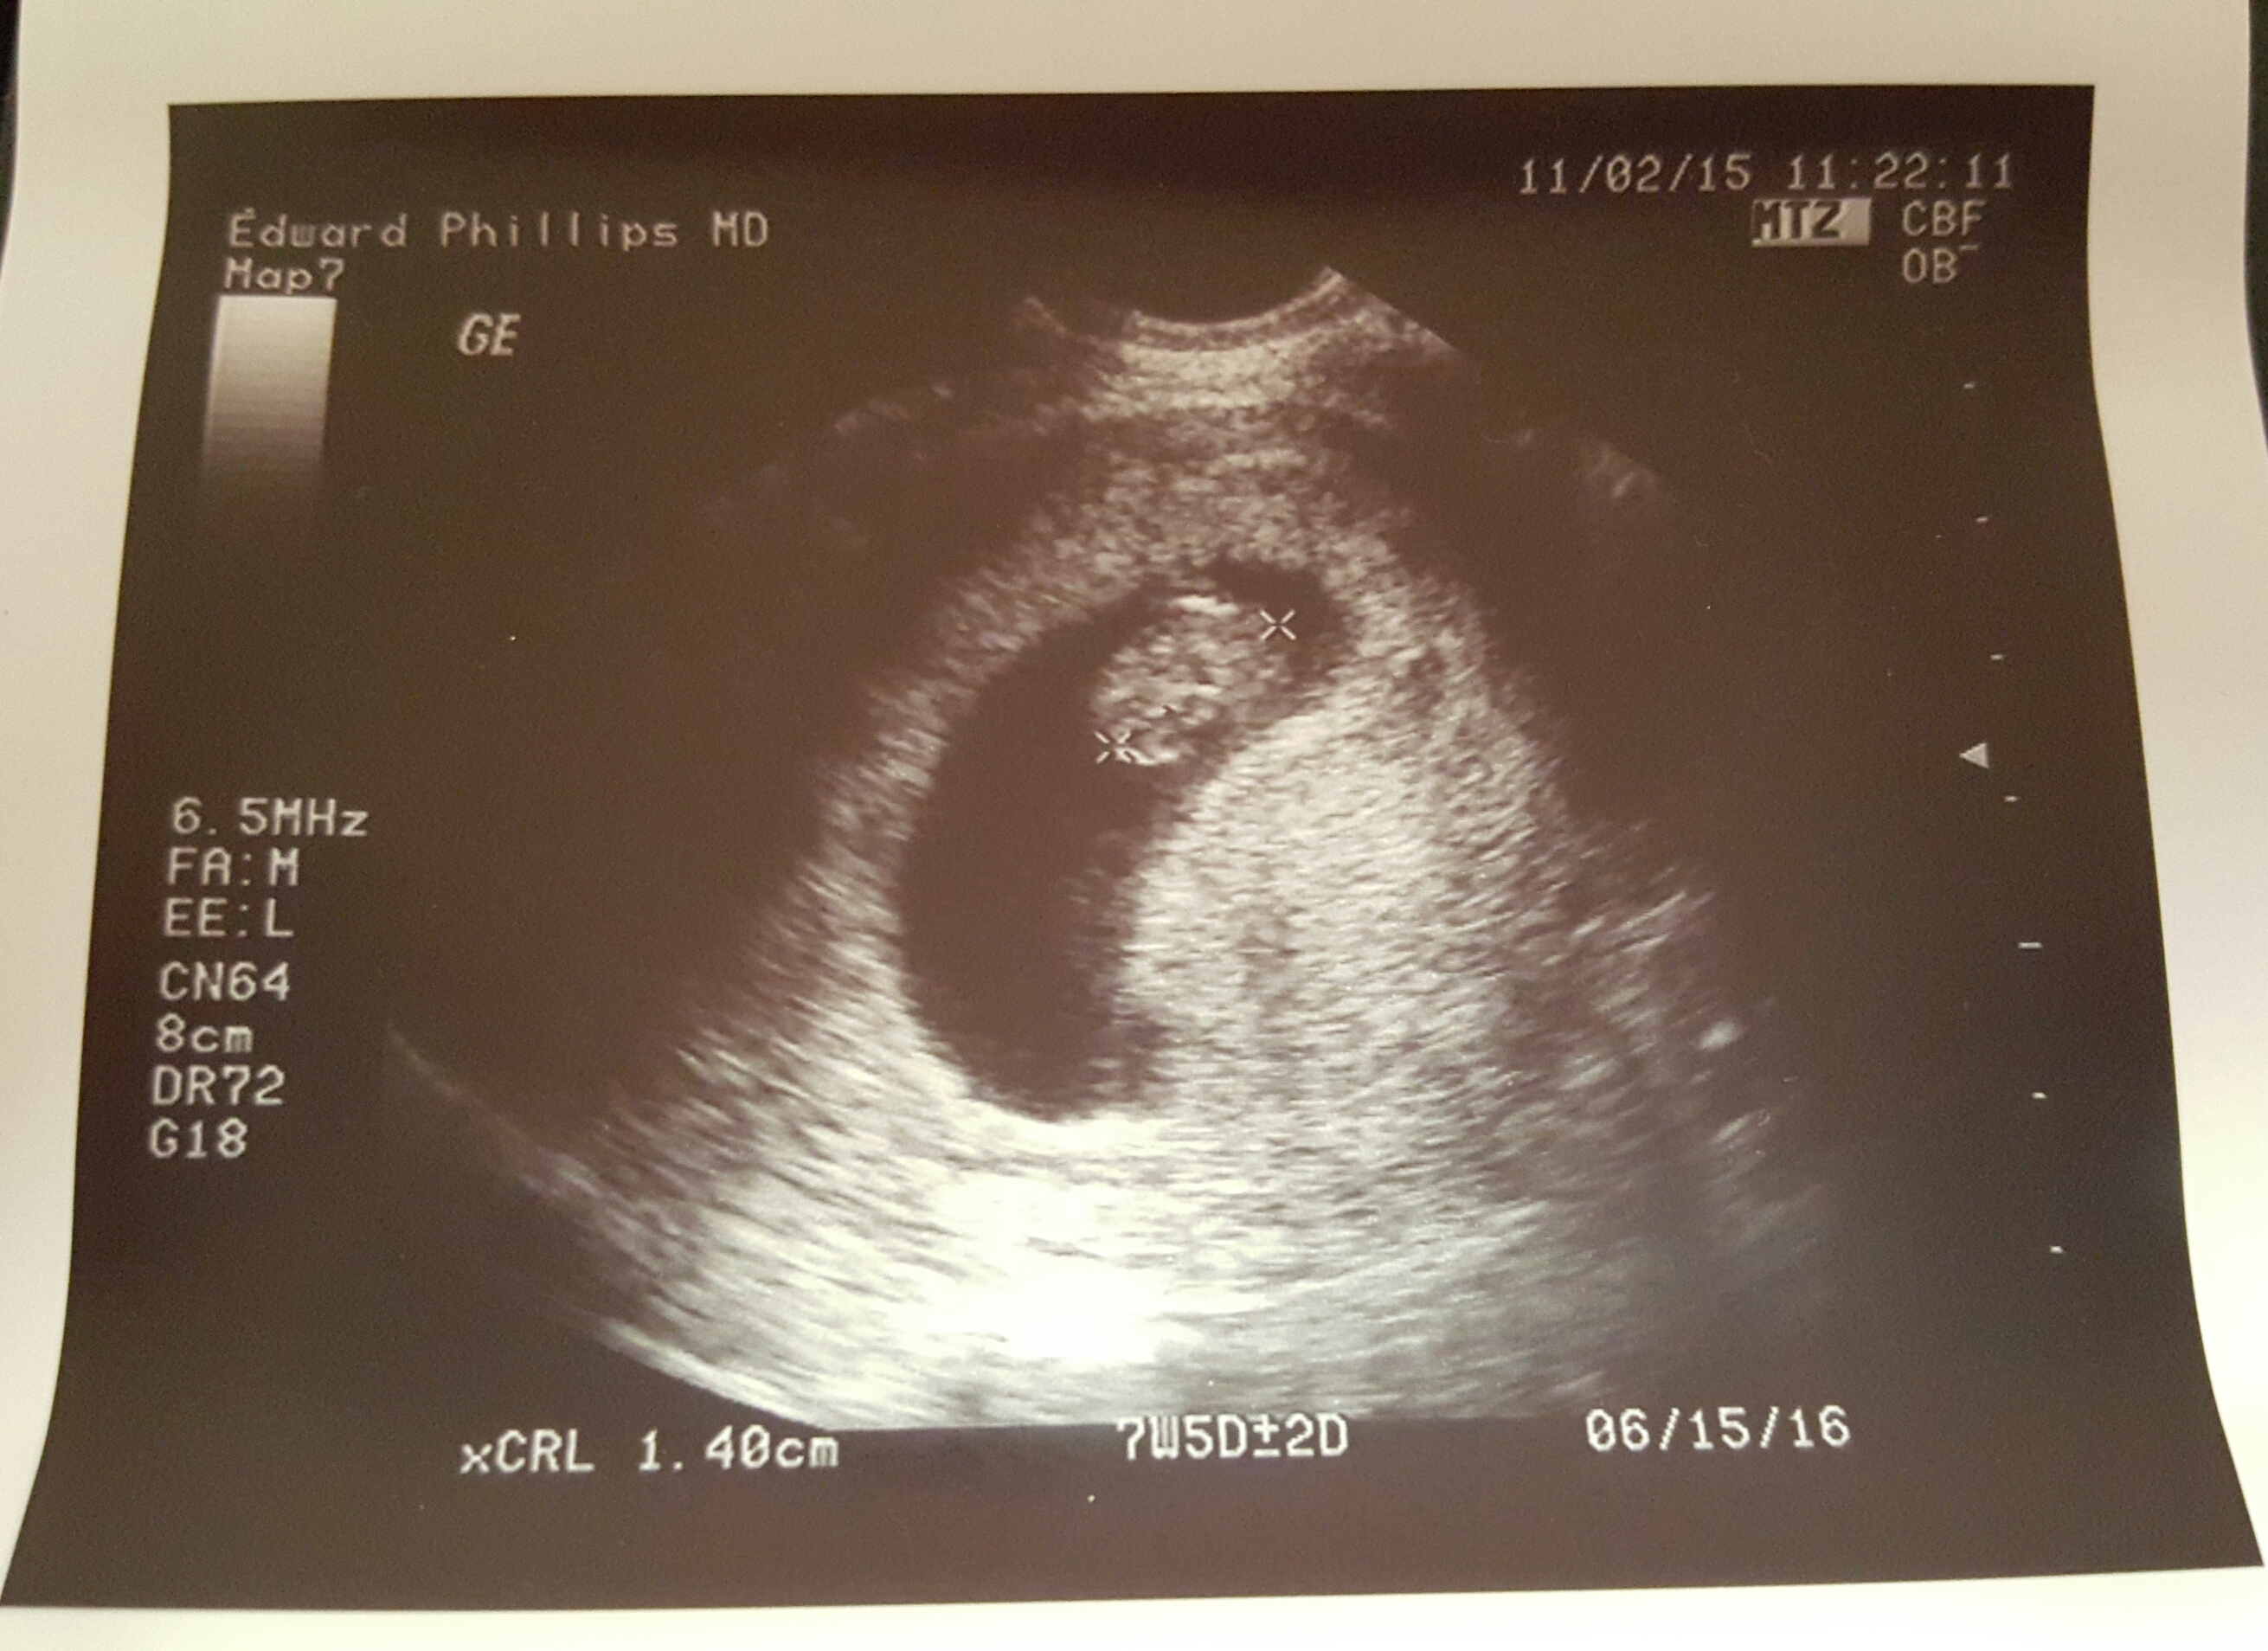

FTM... We had our first US on Monday which was also my birthday ♡ measured at 7w5d. We didn't hear the heartbeat bc the machine didn't have sound, but we could see the little heart fluttering on the monitor. So exciting, scary, emotional. Going back in about 2 weeks for the genetic screening/gender blood work & the next US will be at 12 weeks.